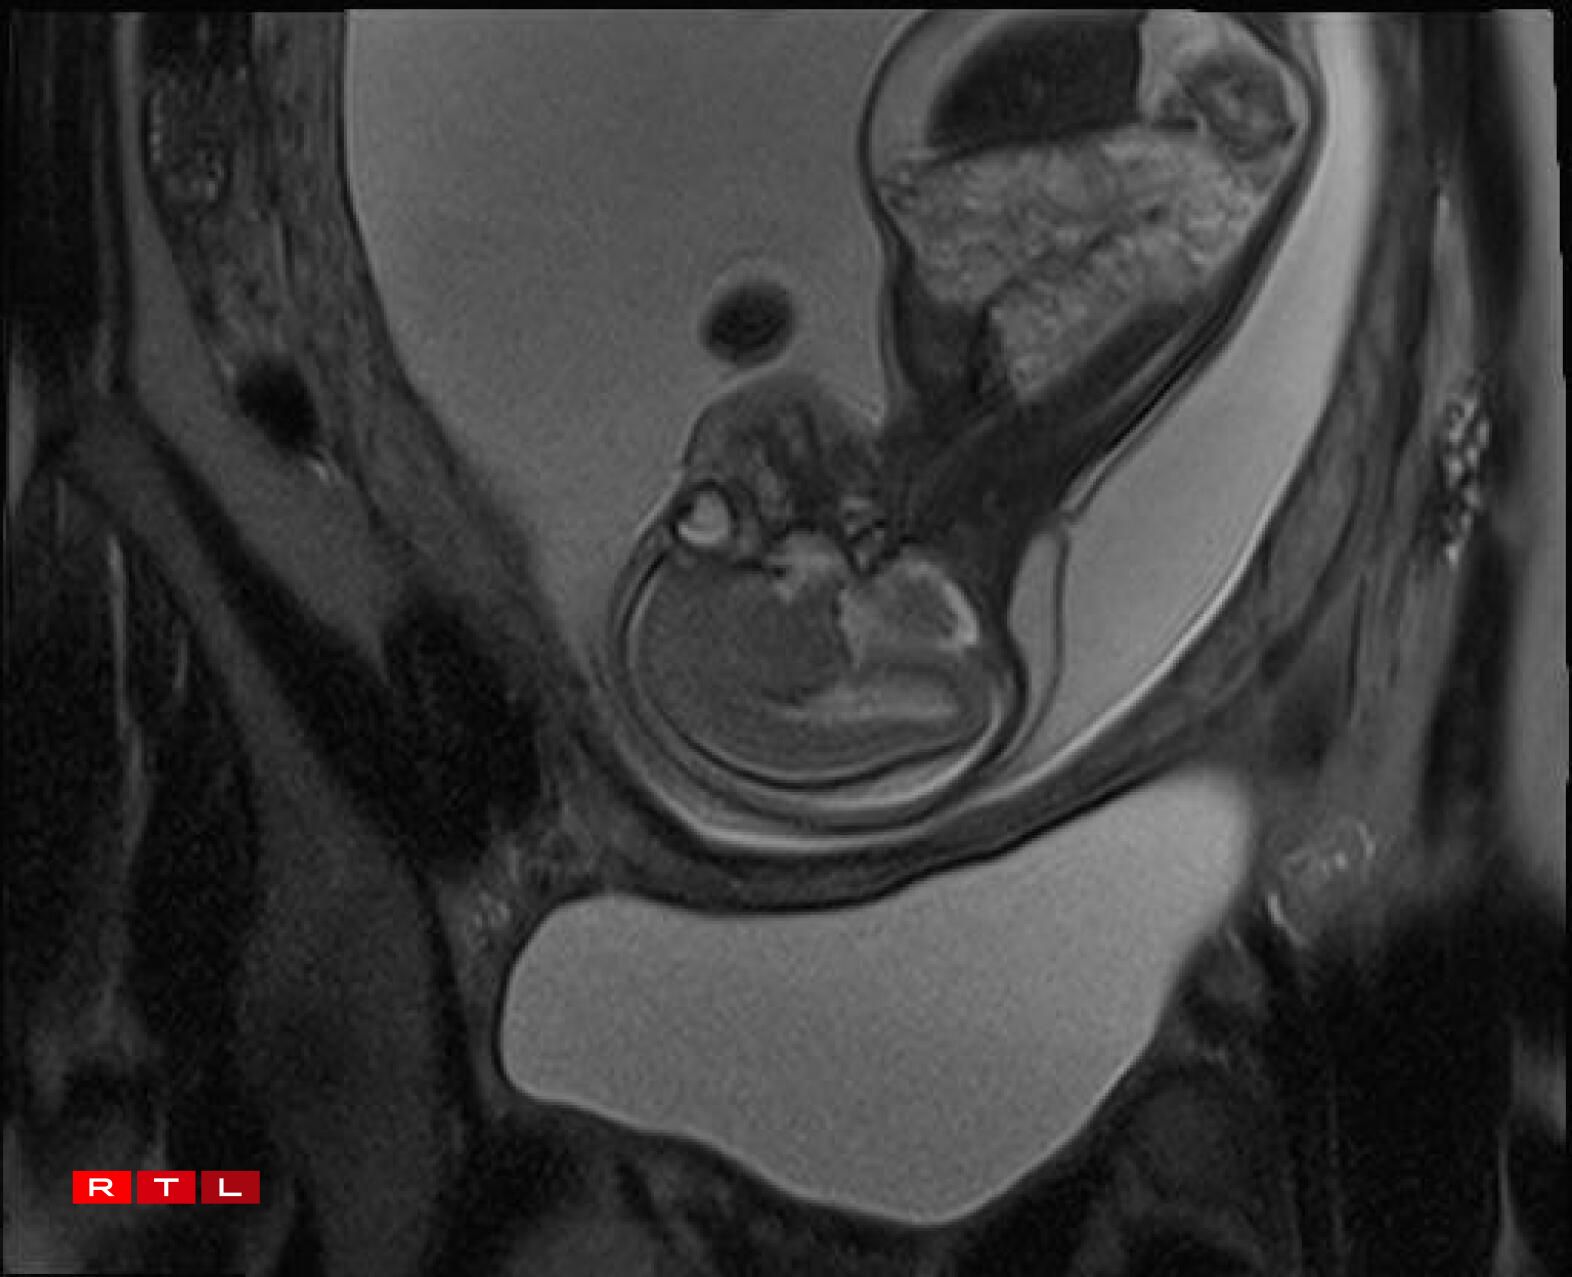

Lis was therefore referred to the Centre Hospitalier de Luxembourg (CHL), where further examinations led to a diagnosis. Noa was found to have a congenital pulmonary airway malformation (CPAM). Doctors explained that a large mass of cysts had formed in his chest, compressing his heart and disrupting his circulation. This, in turn, caused the fluid retention observed during the initial scan.

“On 29 October, we went to Brussels and the doctor said straight away that it was not looking good at all”, Lis recalled. “The heart was far too compressed. You couldn’t see a lung, only this mass of cysts. She saw no chance and told us to look into an abortion”.

In Noa’s case, the CPAM was caused by a malformed aorta: a blood vessel had branched toward the lungs and was feeding the cysts. The condition is known as a sequestration. Professor Kohl proposed the following intervention:

“He would go through my abdomen with two small incisions to reach the amniotic sac, then pass through Noa’s chest to the heart, where he would cauterise the blood vessel that was feeding the cysts using a small electric current. From there, we could hope that the cysts would shrink and the lung could begin to develop”.